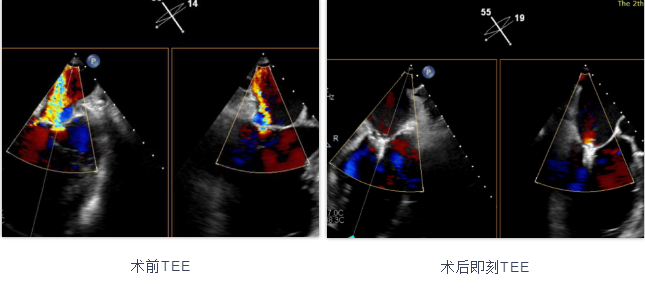

手术患者为81岁男性,术前超声心动图提示左室陈旧性心梗、心尖部室壁瘤形成,左心增大,左室舒张末内径7.2cm,二尖瓣大量反流,三尖瓣中-大量反流,重度肺动脉高压,外科手术风险高。经指南推荐规范用药后和冠脉介入治疗后仍有二尖瓣重度反流,症状没有改善,三尖瓣反流和肺动脉高压分别降至中度。手术采用经股静脉入路穿刺房间隔,在经食道超声心动图和X射线引导下植入一枚DragonFly™瓣膜夹,术后即刻二尖瓣反流降至1+,二尖瓣瓣口双孔化形成,左房压从28mmHg降至8mmHg,二尖瓣平均跨瓣压差2mmHg,器械操作时长为80分钟。该手术的顺利实施,证实了经股静脉二尖瓣缘对缘修复术对于由心肌缺血造成的功能性二尖瓣反流患者有良好治疗效果。